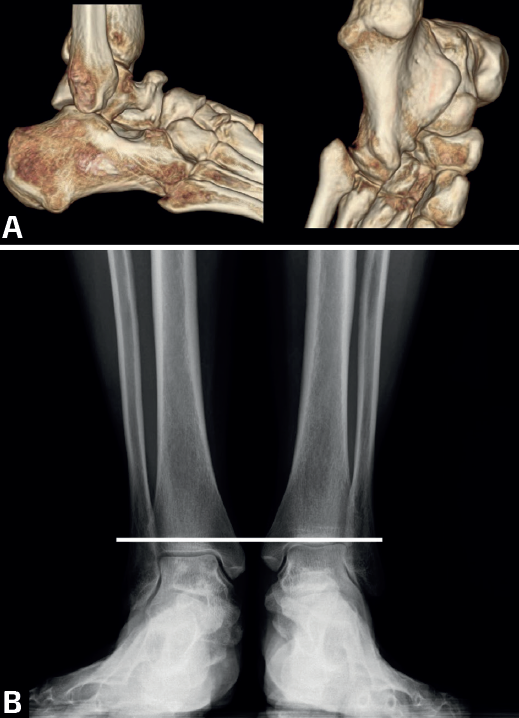

- Múltiples/Masivas: las coaliciones tarsales múltiples/masivas (dos o más de dos en el mismo pie) pueden presentarse como casos aislados no sindrómicos o asociados a otros problemas dentro de un síndrome (Figura 4). Se han descrito casos no sindrómicos de coaliciones combinadas calcaneonavicular, talonavicular y talocalcánea, con frecuencia bilaterales(26,50), y también afectando a la articulación tarsometatarsal(51). La mayoría son asintomáticas y algunas cursan con inestabilidad y entorsis de repetición en el paciente adolescente(50). En algunos casos observamos que la clínica depende del desarrollo de reacciones de estrés en los huesos limítrofes, como en el caso de un paciente con coaliciones tarsales talocalcáneas y naviculocuboideas y con dolor en la cuña intermedia(52). Aunque la mayoría mejoran con tratamiento conservador, existen casos publicados con cirugía de resección con mejoría de los síntomas(50,53,54,55,56,57). En muchas coaliciones múltiples/masivas del tarso, el tobillo (tibiotalar) tiene que adaptarse para poder trabajar como una tibiotalar y una subtalar a la vez, lo que conlleva un crecimiento adaptado a la función, formándose un tobillo cóncavo-convexo (ball and socket en la literatura anglosajona)(58)(Figura 5). En la mayoría de los casos, el hallazgo es casual y el paciente está asintomático. En línea con otras coaliciones, en los pacientes sintomáticos la clínica deriva de un pie plano-valgo. Las soluciones mecánicas consisten en el uso de plantillas con un buen gradiente supinador o en una cirugía de realineación mediante una osteotomía supramaleolar de cierre con base medial(59,60). En algunos pacientes con artrosis subtalar o tibiotalar avanzadas, los procedimientos de realineación pueden combinarse con artrodesis(61,62).